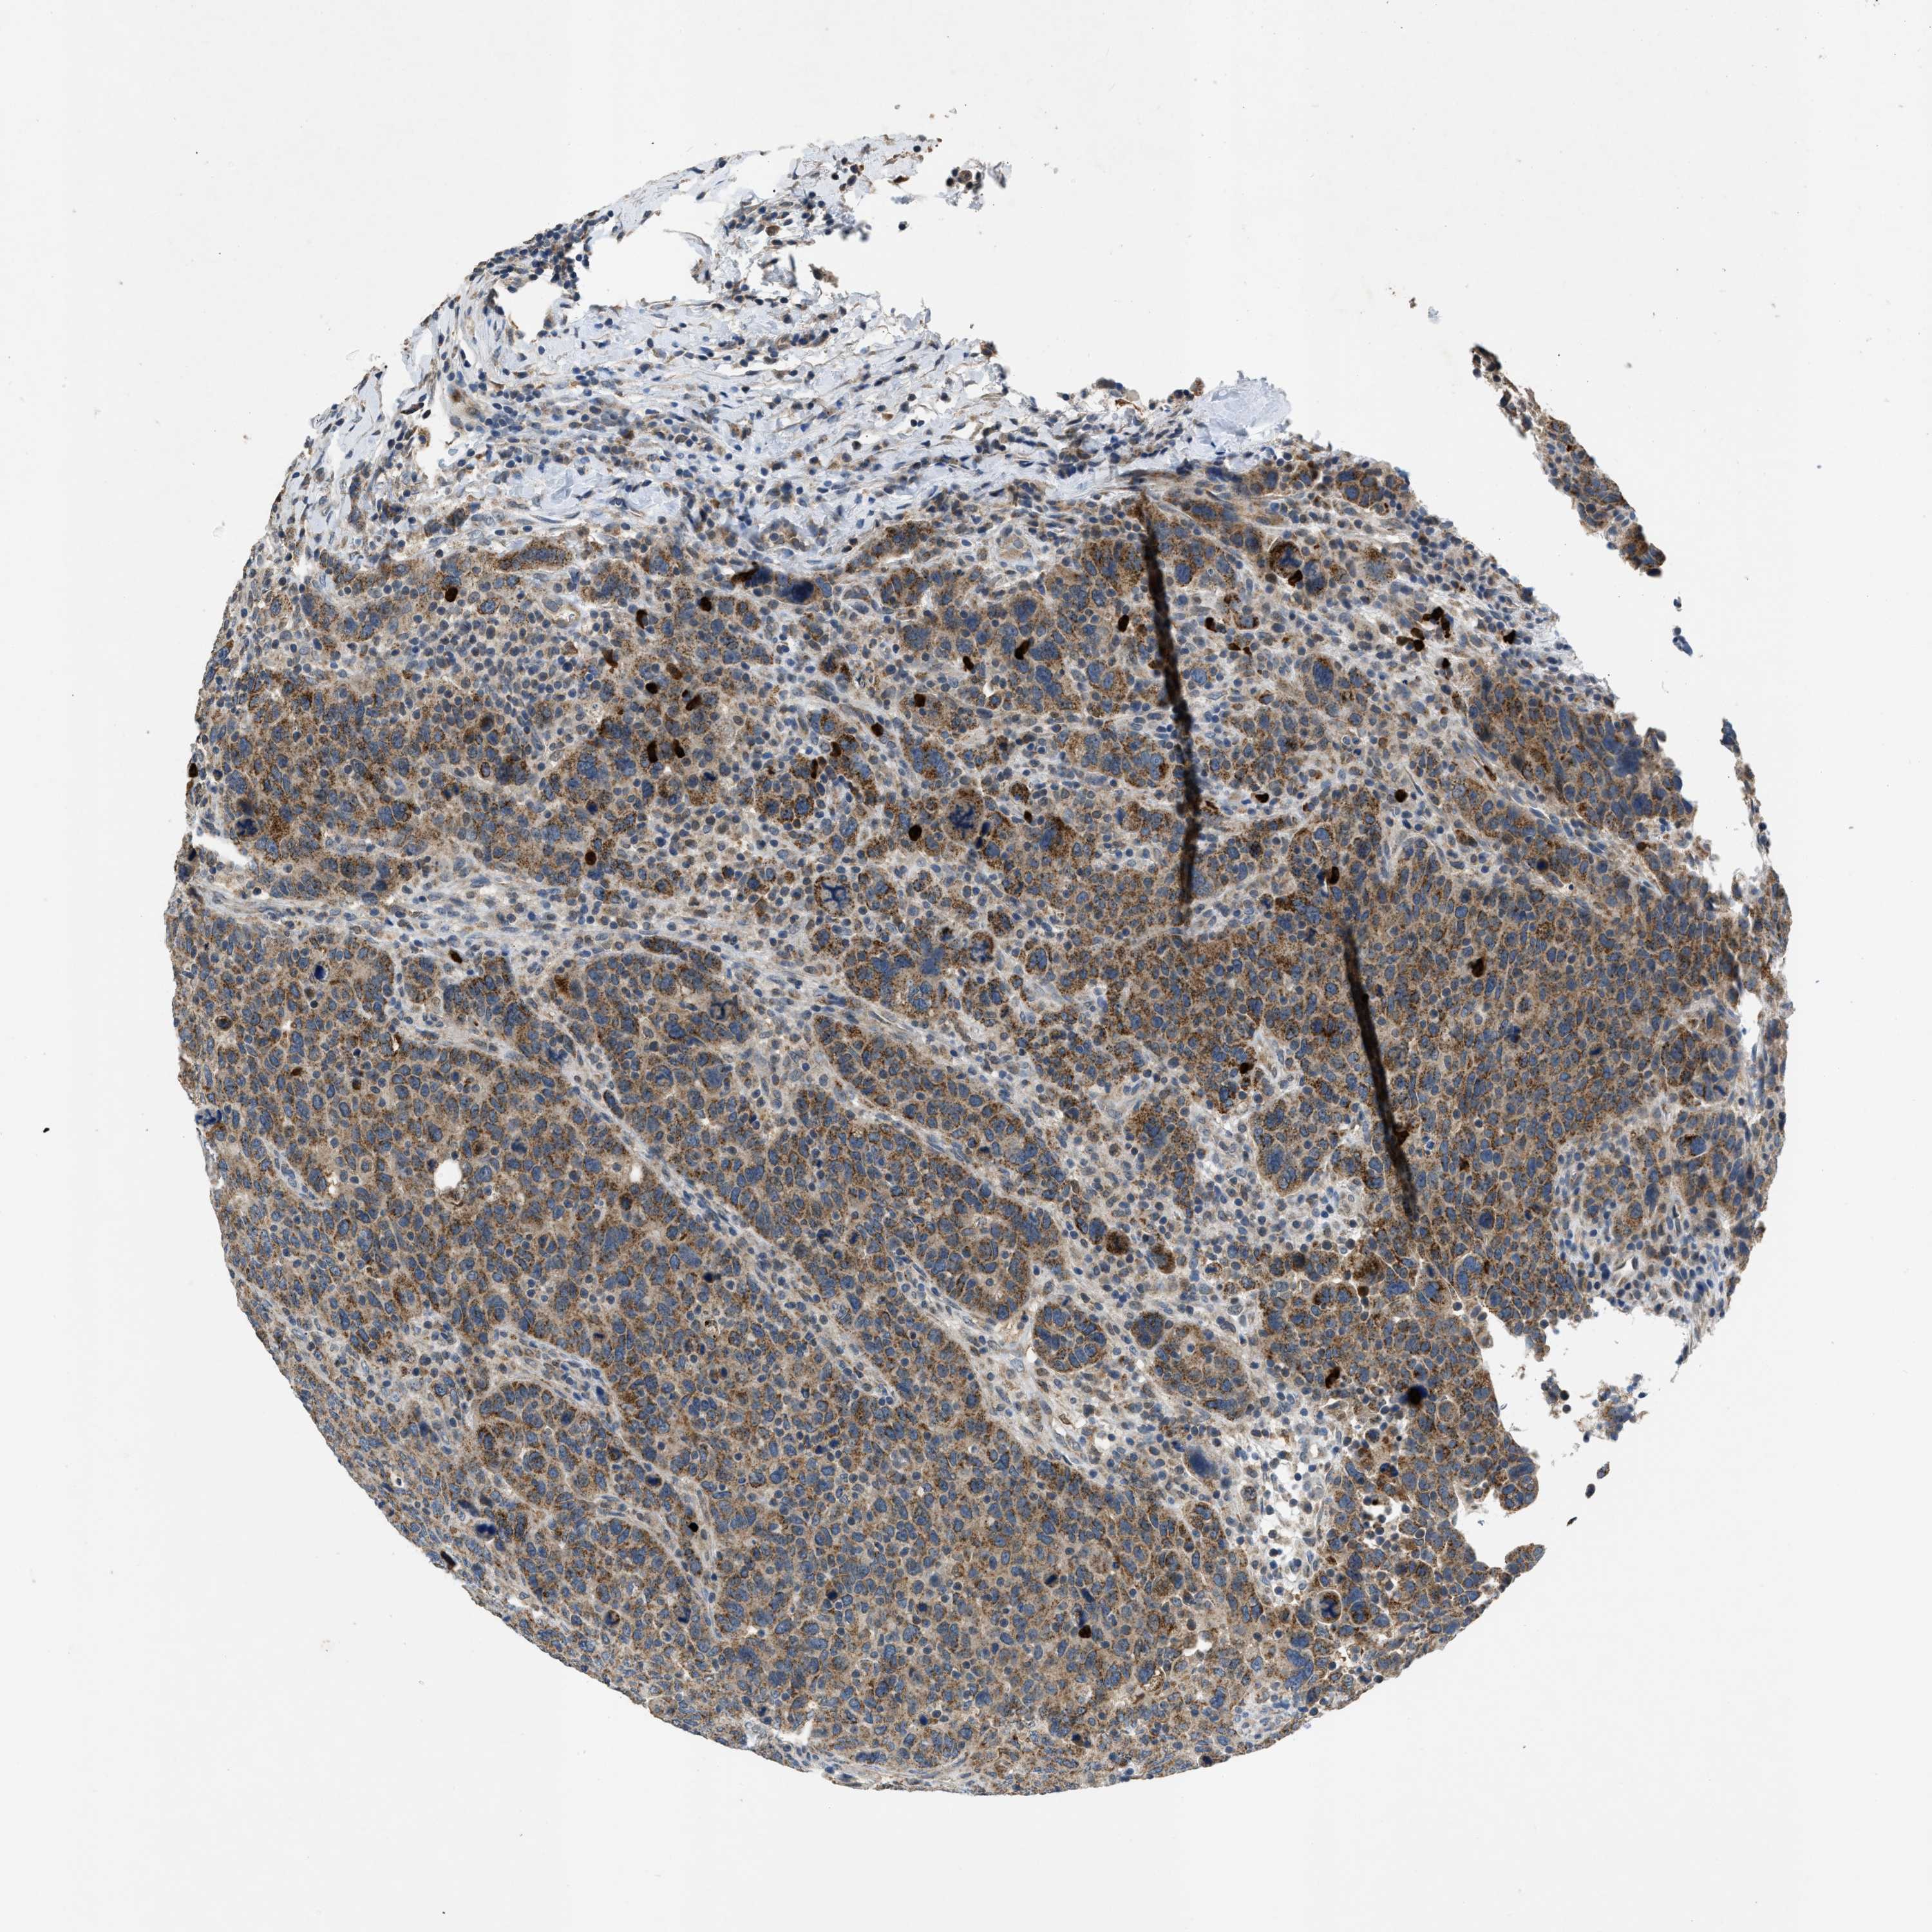

BRCA TCGA BRCA VALIDATION PROTEIN EXPRESSION

Breast cancer

Human cancer